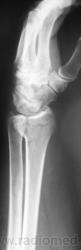

Катенёв Валенти... Дата публикации 12.01.2010, 17:50 Случай 1. Пациент направлен хирургом на рентгенографию лучезапястного сустава. Втр, 12/01/2010 - 18:02 #1 Катенёв Валенти... Не на сайте Был на сайте: 7 лет 3 недели назад Зарегистрирован: 22.03.2008 - 22:15 Публикации: 54876 Случай 2. Пациент направлен на рентгенографию лучезапястного сустава. Comment Upload: Втр, 12/01/2010 - 18:09 #2 Катенёв Валенти... Не на сайте Был на сайте: 7 лет 3 недели назад Зарегистрирован: 22.03.2008 - 22:15 Публикации: 54876 Случай 3. Пациент направлен на рентгенографию плечевого сустава. Comment Upload: Ср, 13/01/2010 - 17:31 #3 Ольга Дмитриевна Не на сайте Был на сайте: 15 лет 9 месяцев назад Зарегистрирован: 13.01.2010 - 16:55 Публикации: 168 По поводу случая 1. С лучом все понятно, а вот переломовывих ладьевидной кости? Как думаете? Красота - гормон карьерного роста! Ср, 13/01/2010 - 22:53 #4 Катенёв Валенти... Не на сайте Был на сайте: 7 лет 3 недели назад Зарегистрирован: 22.03.2008 - 22:15 Публикации: 54876 А вот как трактовать в случае 2 перелом? Ср, 13/01/2010 - 23:47 #5 Ольга Дмитриевна Не на сайте Был на сайте: 15 лет 9 месяцев назад Зарегистрирован: 13.01.2010 - 16:55 Публикации: 168 В случае 2 - на мой взгляд внутрисуставной перелом задненаружного края дист эпифиза лучевой кости. Что за +ткань по нар краю эпифиза луча - сложно сказать, мож ломал раньше. Красота - гормон карьерного роста! Ср, 13/01/2010 - 23:48 #6 Ольга Дмитриевна Не на сайте Был на сайте: 15 лет 9 месяцев назад Зарегистрирован: 13.01.2010 - 16:55 Публикации: 168 Что скажете по поводу случая1? Красота - гормон карьерного роста! Чт, 14/01/2010 - 18:17 #7 Глазков Игорь А... Не на сайте Был на сайте: 9 месяцев 2 недели назад Зарегистрирован: 19.12.2008 - 20:41 Публикации: 1597 оскольчатый перелом лучевой кости. Прийди к Себе Пт, 15/01/2010 - 22:26 #8 Катенёв Валенти... Не на сайте Был на сайте: 7 лет 3 недели назад Зарегистрирован: 22.03.2008 - 22:15 Публикации: 54876 "Красиво" упал. "Красивый" перелом Comment Upload: Вс, 17/01/2010 - 09:48 #9 Катенёв Валенти... Не на сайте Был на сайте: 7 лет 3 недели назад Зарегистрирован: 22.03.2008 - 22:15 Публикации: 54876 Случай 5. Comment Upload:

По поводу случая 1. С лучом все понятно, а вот переломовывих ладьевидной кости? Как думаете?

Что скажете по поводу случая1?

оскольчатый перелом лучевой кости.

"Красиво" упал. "Красивый" перелом